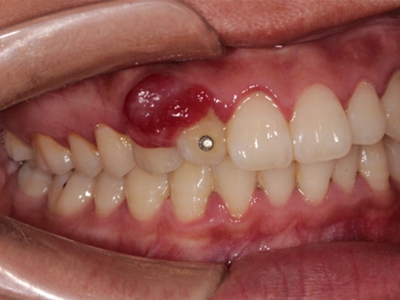

牙龈炎是发生于牙龈组织的炎症,患者可出现牙龈出血伴肿胀、发红、正常形态改变和偶尔不适等症状。本病主要由口腔卫生状况差导致,包括口腔不洁、牙菌斑等,诊断依据临床检查,治疗包括专业牙齿清洁和加强家庭口腔卫生。

牙龈炎可先引起牙齿与牙龈之间的沟(龈沟)加深,然后牙龈充血,炎症围绕一个或多个牙齿,伴牙龈乳头肿胀和易出血。一般无痛,可自行消退,也可维持轻度炎症数年。